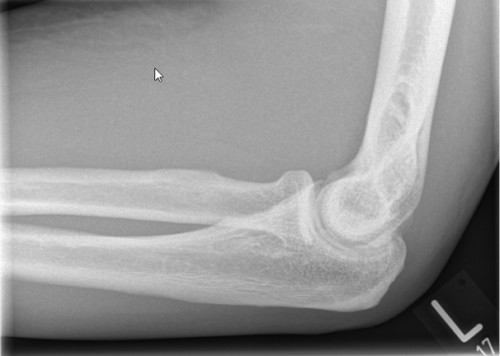

Ein 54 Jahre alter Patient stellt sich bei Ihnen in der Notfallambulanz vor. Er erzählt vor 5 Tagen bei seiner Tätigkeit als Postbote gestolpert und nach hinten gefallen zu sein. Dabei habe er seinen Arm nach hinten geschwungen um sich abzufangen und dabei einen stechenden Schmerz verspürt. Er war bereits am Unfalltag bei einer Kollegin von Ihnen in der Nofallambulanz. Diese hatte eine Schwellung und ein Hämatom am Unter- und Oberarm medialseitig inspektorisch, sowie ein Kraftdefizit beim Heben im Ellenbogen festgestellt. Im daraufhin angefertigten Röntgenbild (siehe unten) wurde keine Fraktur festgestellt. Daraufhin wurde ein Oberarm-Cast angelegt und dem Patienten ein zeitnaher MRT-Termin organisiert. Nun stellt sich der Patient zur Befundbesprechug und Planung des Procedere vor. Nach Abnahme der Gipsschiene sehen Sie folgenden Inspektionsbefund.